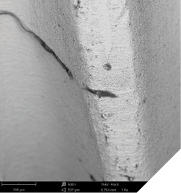

Peri-implantitis represents a significant challenge in modern dentistry, threatening the long-term success of dental implants and patient oral health (Fig. 1). This inflammatory condition, affecting tissues surrounding dental implants, leads to progressive bone loss and eventual implant failure if left untreated. Systematic reviews indicate an alarming overall prevalence of 19.53% at the patient level and 12.53% at the implant level, highlighting the scale of this clinical challenge.1 While multiple risk factors contribute to peri-implantitis, including poor oral hygiene, smoking, and history of periodontitis, emerging research has identified implant surface contamination as a critical yet preventable contributor to these complications. The clinical relevance of this factor was substantiated in various quality assessment studies over the past 10 years analyzing hundreds of commercially available implants.2-5 On average, one in four tested implants showed significant impurities with more than 50 plastic particles, most of them small enough for phagocytosis by immune cells (Figs. 2-12).

Fig. 2